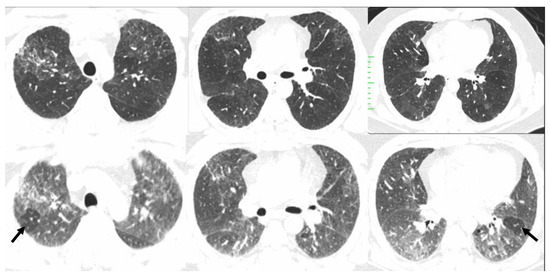

Three categories of NFHP (Table 3, Figure 8) and FHP (Table 4, Figure 9, Figure 10, Figure 11 and Figure 12) have been described.

Figure 8. Typical non-fibrotic HP. Inspiratory phase CT (top row) shows ground glass opacities (red arrows) and expiratory phase CT (bottom row) shows air trapping (yellow arrows). Note the diffuse axial and craniocaudal distribution.

Figure 9. Typical fibrotic HP. Baseline CT (A) shows patchy GGOs. Follow up CT 3 years later (BD) shows traction bronchiectasis (curved arrow), reticulations, patchy GGOs, and consolidations. Random axial and craniocaudal distribution of fibrosis. Axial inspiratory (C) and expiratory phase (D) shows three-density sign with expected increased attenuation of normal lung (short arrows) and GGOs (black asterisk). Lucent areas of decreased attenuation and vascularity depict air trapping (long arrow).